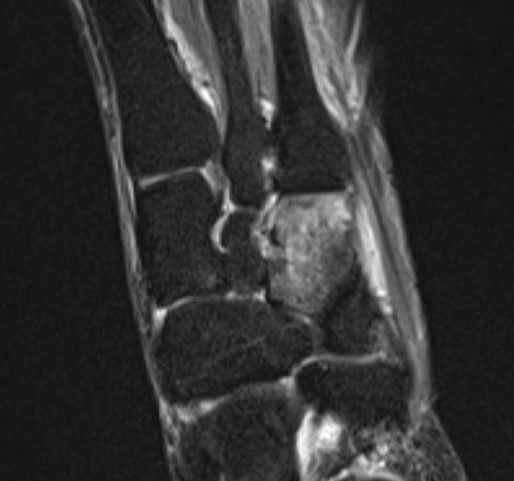

Knochenmarkoedem isoliert os cuneiforme laterale